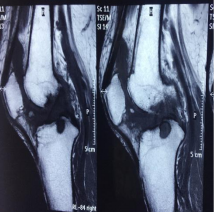

於2017年10月21日,PURECELL集團接待了這位F女士,且經PURECELL醫療專家面診後,確認可能進行UCF膝關節修復,並由PURECELL首席醫療專家Dr. Ian Chinsee對F女士進行了UCF膝關節靶向性注射修復。據F女士的反饋結果,在接受UCF膝關節靶向修復一個月後,F女士雙膝關節疼痛基本消失,夜間勿需服用安眠藥和強力止疼藥,同時可擺脫輪椅直立行走。三個月後F女士反饋,雙膝關節已無疼痛感,生活恢復正常,行走正常,再也不用電動輪椅和枴杖輔助了。2018年12月,距離F女士治療後已過去一年有餘,通過F女士反饋的MRI影像報告顯示,我們醫療專家驚喜發現,F女士的雙膝關節骨密度在逐漸恢復,撕裂的半月板已經粘合,軟骨部位清晰可見,軟骨面恢復光滑,雙膝關節恢復至較好的狀態。

在一個偶然機會,她瞭解到PURECELL集團的UCF細胞因子膝關節靶向修復療法,就這樣,經PURECELL澳洲醫療專家詳細診斷MRI影像報告後,同意這位女士進行UCF膝關節修復。並由PURECELL首席醫療專家Dr. Ian Chinsee親自給這位女士進行雙膝關節修復。根據反饋,在修復3個月後,該女士的雙膝關節部位疼痛感消失,腿部肌肉通過PURECELL專業膝關節康復鍛煉亦在恢復中,膝關節部位未發現腫脹。根據該女士提供的2018年10月26日最新MRI報告顯示: 炎症和積液基本消失,骨密度開始恢復,半月板,軟骨部位清晰可見,逐漸恢復重建。PURECELL醫療專家建議,UCF修復效果非常明顯,可持續觀察3個月後,再做一次MRI對比。這位遭受了20多年的膝關節疼痛折磨的女士,在這一刻終於面露笑容,表示待修復後再做一次UCF膝關節修復鞏固效果。